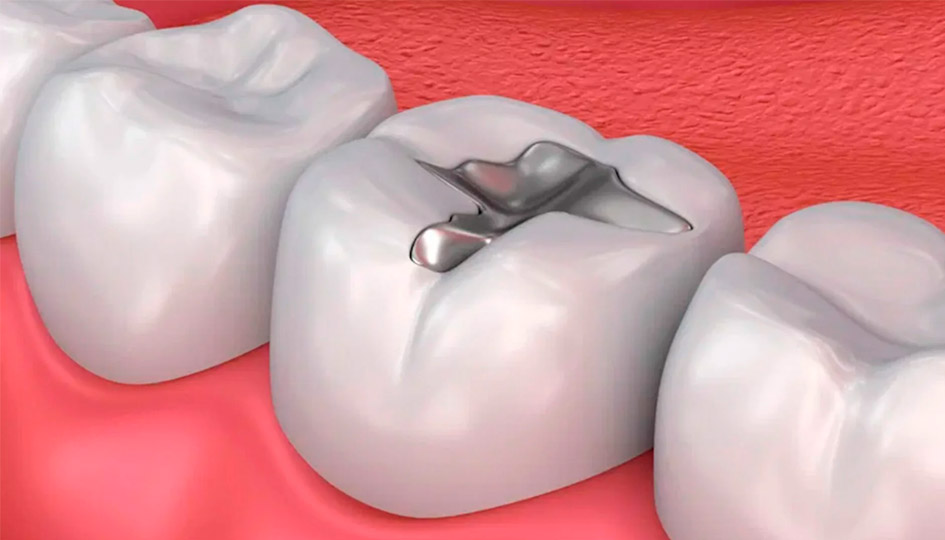

EMPASTES Y

OBTURACIÓN

También conocido como empaste dental, se trata de eliminar la caries con el fin de evitar que ésta avance, evitando así la realización de una endodoncia o en algunos casos la extracción de la pieza.

Protocolo de retirada de empastes de amalgama de mercurio

El protocolo SMART (técnica segura de eliminación de amalgamas de mercurio)

es un método de protección estandarizado para eliminar de forma segura los empastes de amalgama